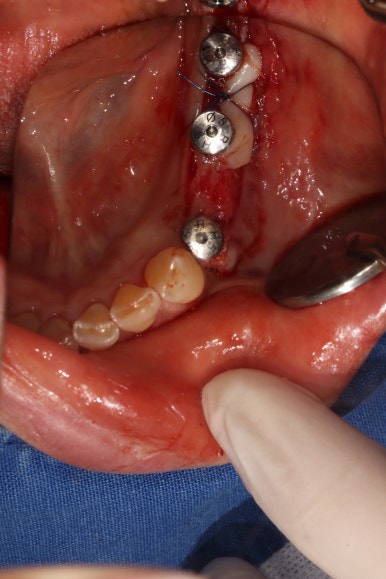

임플란트 1차수술

이렇게 예쁘게 3개의 임플란트를 심어드렸습니다.

뼈이식을 하여야 하는 경우의 임플란트 1차 수술은

치유지대주가 (healing abutment) 아닌 커버스크류(coverscrew)를 장착한채로 마무리 됩니다.

먼저 부분층 판막 (partial thickness flap)을 예쁘게 형성하여,

골막이 드러나는 환경을 만들어 줍니다.

원하는 크기를 선택하여 치유지대주를 연결해 줍니다.